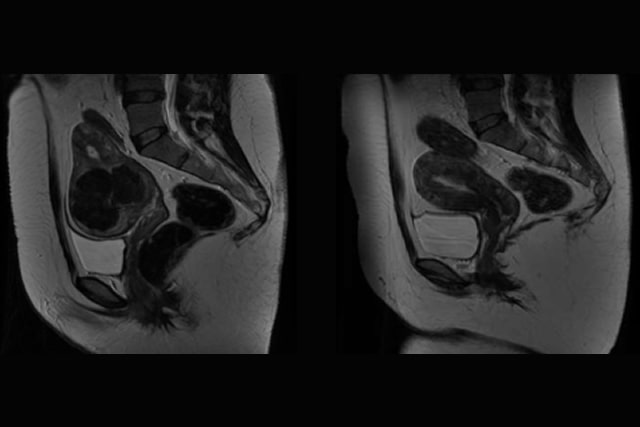

Ecografía Ginecológica Doppler 3D - Elastografía para valoración de miomas, dos novedades en el tratamiento de miomas. Nos permite ver el útero con una definición casi real.

En mi tesis Doctoral, presentada en 2006, premio a la mejor Tesis Doctoral en Cirugía de la Universidad Complutense de Madrid y premio del FISCAM (Fundación para la Investigación Sanitaria de Castilla la Macha) a la mejor Tesis Doctoral de Castilla-La Mancha, validé el diagnóstico y seguimiento de los miomas con embolización uterina con Eco-Doppler frente a la RNM (Resonancia Nuclear Magnética).

Este hecho es muy importante para las pacientes puesto que demuestra que ambas pruebas son igualmente eficaces en esta patología, evitando métodos diagnósticos más costosos e incómodos para las pacientes.